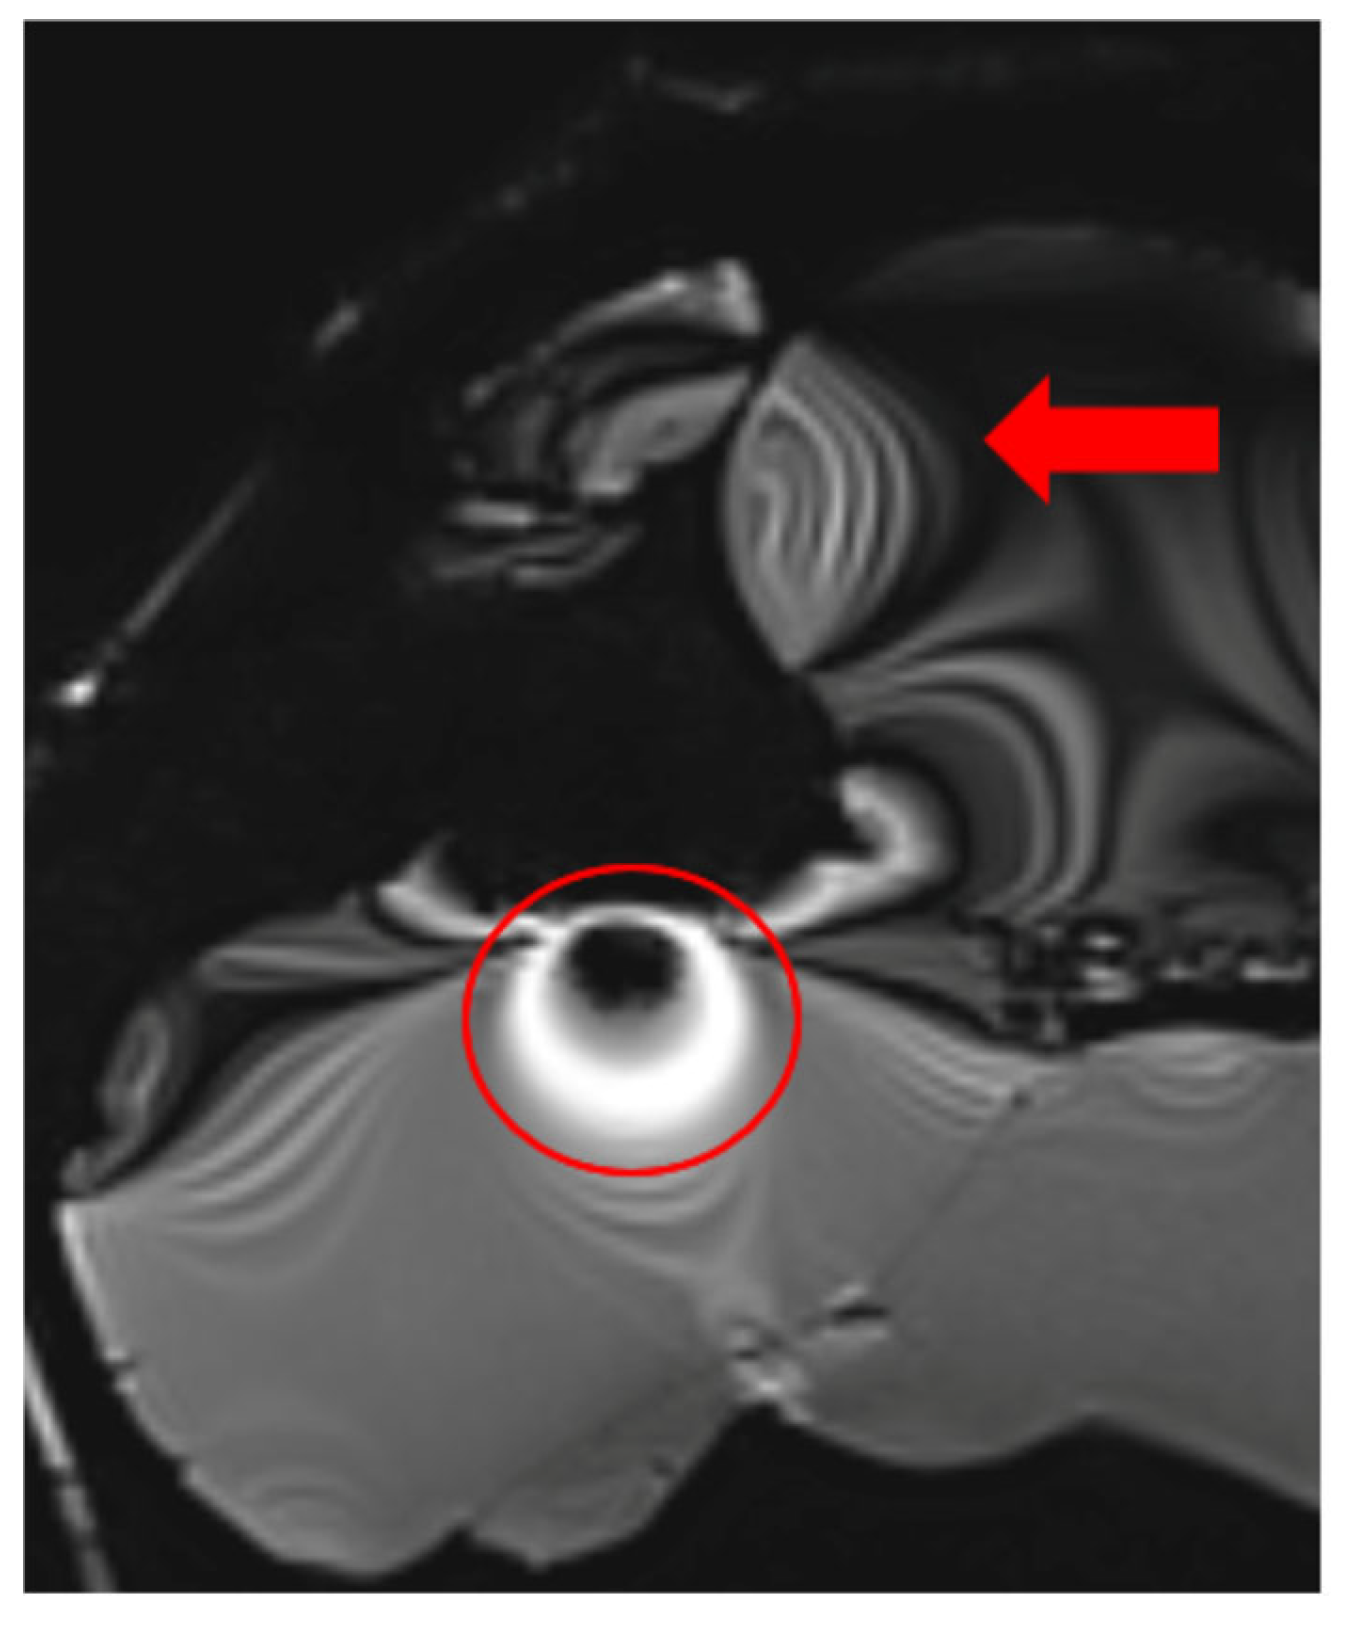

3.1. Types and Causes of MRI Artifacts

3.2. Artifact Suppression Techniques

3.3. Radiofrequency (RF) Artifacts and Signal Homogeneity

3.4. Turbo Spin Echo (TSE) for Artifact Reduction

3.5. Fat Saturation Artifacts

3.6. Optimized Imaging Sequences for Tumor Detection Under Cranial Implants